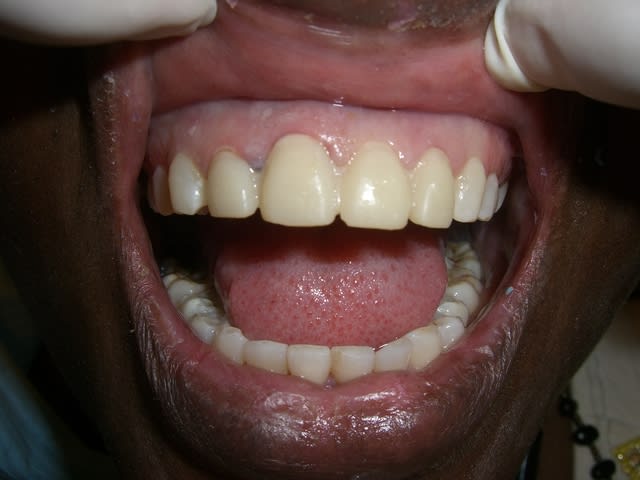

10/07/2012 à 23h01

Je déterre mon poste en mettant les photos du cas. Désolé il manque le principal: la photo de l'état initial...

Je n'ai pas osé faire que de l'Emax. J'ai décidé avec le labo de faire une armature Zircone avec de l'Emax pressée dessus.

Il y a les photos du biscuit, du bridge fini le jour de la pose et à 3 semaines.

A vos critiques, merci!

10/07/2012 à 23h39

C'est très beau.

De ce que l'on peut en voir, c'est beau et propre.

je trouve le résultat très esthétique ;)